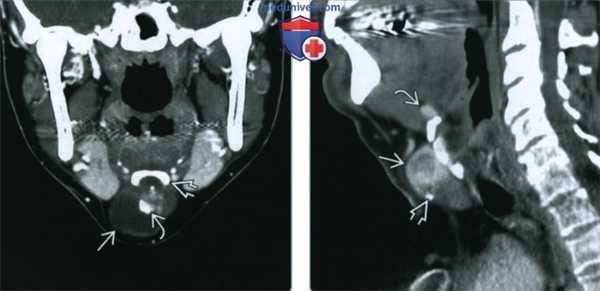

(Слева) КТ с КУ, коронарная проекция. Срединное кистозное образование шеи, которое плотно спаяно с подъязычной костью. У верхнего края кисты имеются плотные кальцификаты и накапливающий контраст мягкотканный компонент.

(Справа) КТ с КУ, сагиттальная реконструкция. Солидное неоднородное образование? расположенное сразу ниже подподъязычной кости, у нижней части которого имеются кальцификаты. Над подъязычной костью визуализируется небольшой дополнительный остаток эктопированной ткани. Щитовидная железа в своем типичном месте отсутствовала.